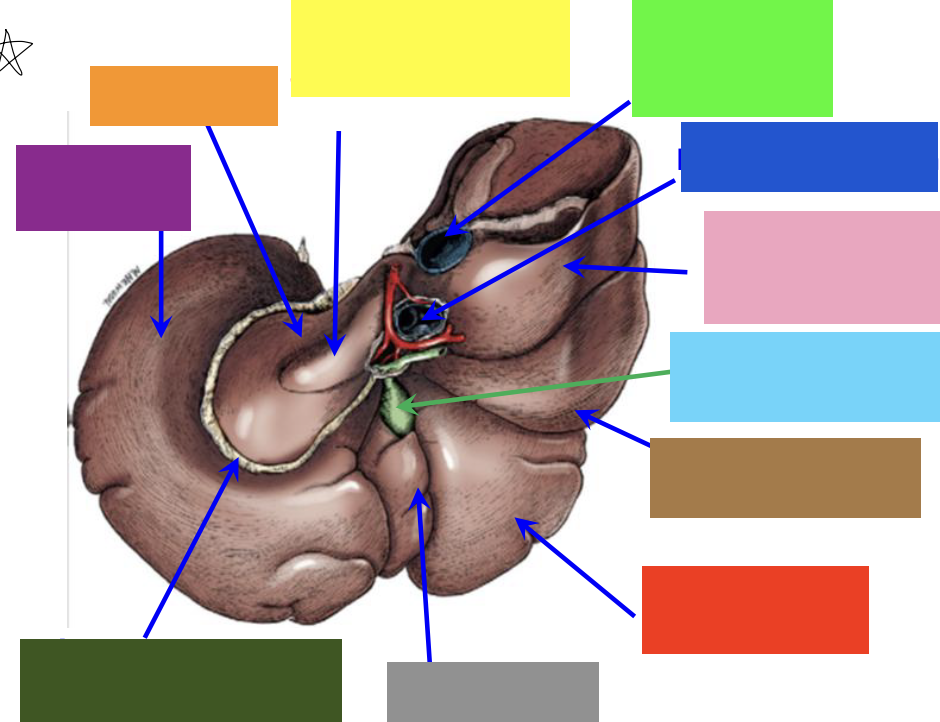

purple box

left lateral lobe

orange box

caudate lobe

yellow box

papillary process of the caudate lobe

neon green box

right lateral lobe

dark blue box

hepatic portal vein

pink box

caudate process of the caudate lobe

light blue box

gall bladder

brown box

right lateral lobe

red box

right medial lobe

grey box

quadrate lobe

dark green box

lesser omentum